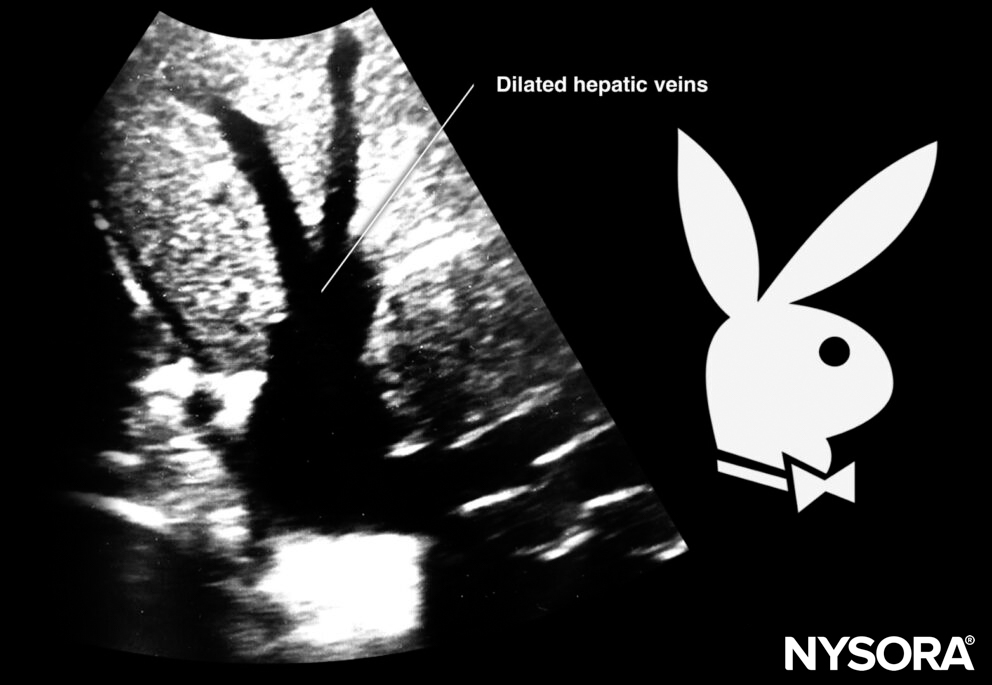

- The inferior vena cava runs intrahepatically and has a hepatic vein branch. In case of a dilated inferior vena cava, the aspect of the inferior vena cava and the hepatic vein is sometimes compared to a ‘Moose head’ or a ‘Playboy bunny’.

Sonoanatomy of dilated hepatic veins.